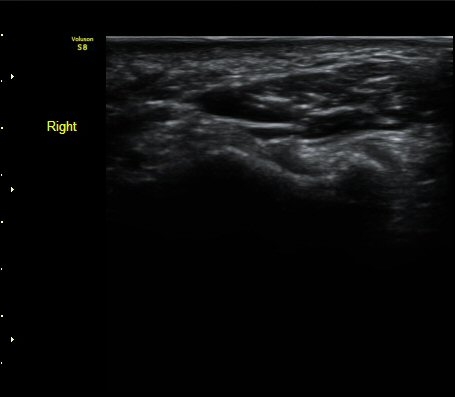

ÄÄÇ»ÅÍ ÃÔ¿µ»ó °¥°í¸®»À °¥°í¸® °ñÀýÀ» º¸ÀÓ(±×¸² 5, 6, 7).